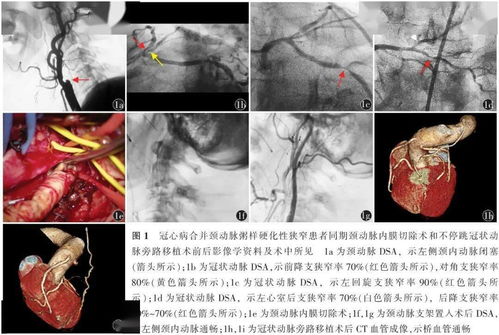

接下来,是一些需要长期控制和管理的心脏病类型。冠心病、慢性心衰等虽然难以完全治愈,但是通过药物、支架植入或搭桥手术,可以稳定病情,显著延长生存期。心脏瓣膜病则可以通过置换手术或药物管理来维持正常的功能。